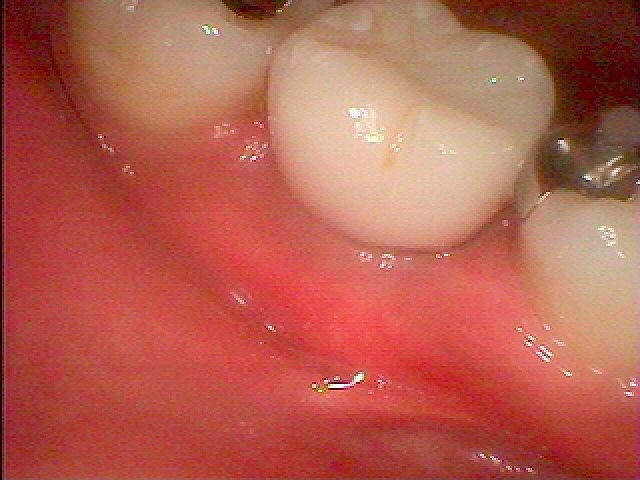

インプラント埋入後2か月になります

抜歯即時インプラント埋入のため抜歯してから2か月ということになります

このように傷がいえています

きれいに治ってきています